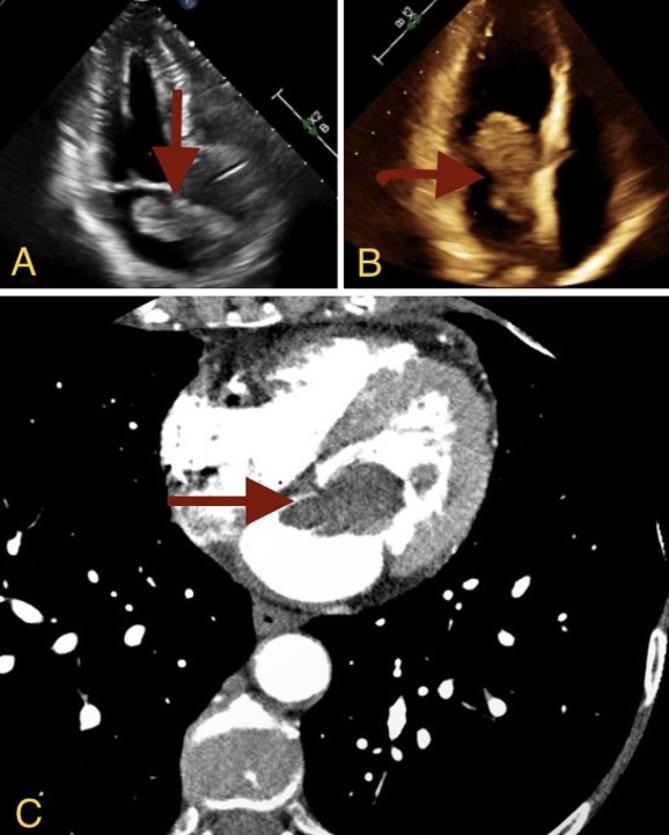

Atrial myxomas are typically found in the left atrium and are the most common among overall rare cardiac tumors. Herein, we describe the clinical course of a 72-year-old female with non-small cell lung adenocarcinoma found to have an atrial mass during an imaging for evaluation for lung cancer progression. Differentiating between distinct types of masses can pose a challenge to the treatment team especially in the setting of exiting malignancy. This case demonstrates the complex decision making involved in the diagnosis, and timing of intervention to remove atrial mass in patients with frailty and a fast-growing cardiac mass.

心房黏液瘤通常位于左心房,是总体罕见心脏肿瘤中最常见的类型。在此,我们描述了一名72岁女性非小细胞肺腺癌患者的临床病程,该患者在评估肺癌进展的影像学检查中发现有心房肿物。区分不同类型的肿物对治疗团队来说可能是一项挑战,尤其是在存在恶性肿瘤的情况下。本病例展示了在诊断以及对体弱且心脏肿物生长迅速的患者进行心房肿物切除干预时机方面所涉及的复杂决策。